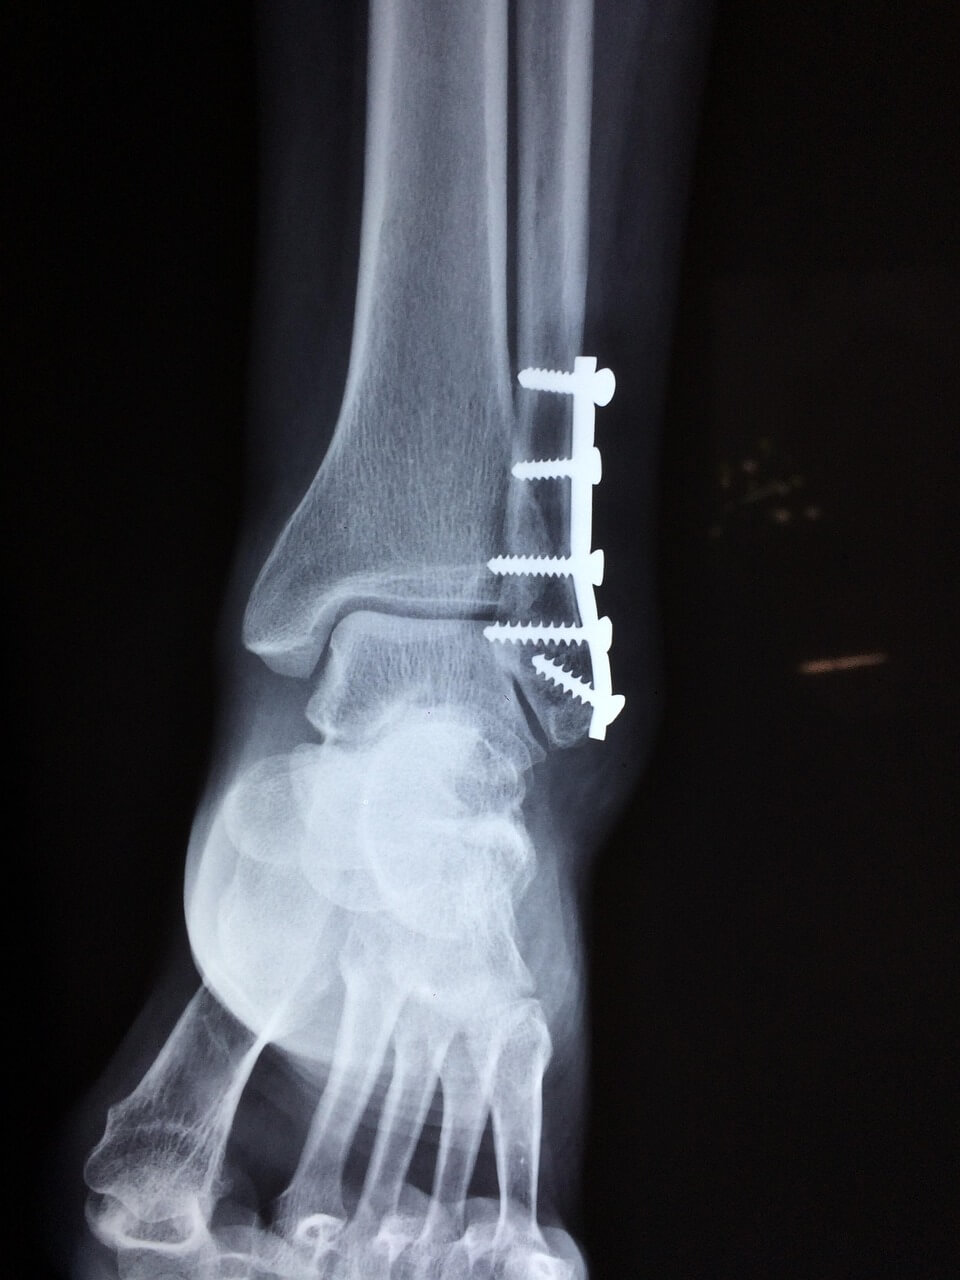

- 수술 고려

3~6개월 표준 재활에도 통증 지속·부분 파열 의심 시 수술적 처치 고려. 이후 단계적 체중부하·관절 가동 범위 복원이 아킬레스건염 예후를 좌우합니다.